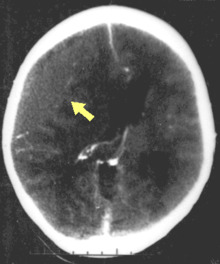

CT scan showing epidural hematoma (arrow)

Diagnosis is suspected based on lesion circumstances and clinical evidence, most prominently a neurological examination, for example checking whether the pupils constrict normally in response to light and assigning a Glasgow Coma Score.[22] Neuroimaging helps in determining the diagnosis and prognosis and in deciding what treatments to give.[75] DSM-5 can be utilized to diagnose TBI and its psychiatric sequelae.[76][77][78]

The preferred radiologic test in the emergency setting is computed tomography (CT): it is quick, accurate, and widely available.[79] Follow-up CT scans may be performed later to determine whether the injury has progressed.[9]